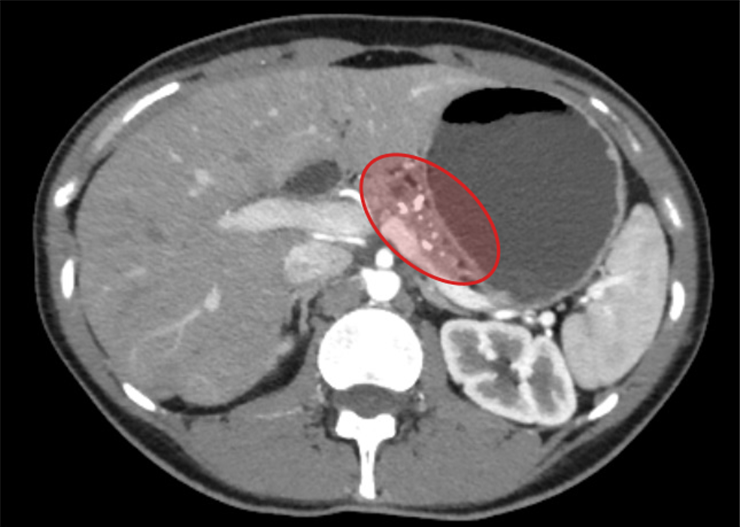

Нещодавно дівчина проходила плановий чек-ап стану здоров’я, і раптова знахідка на УЗД неабияк здивувала лікарів. Дівчину навіть намагались переконати, що каміння все ж таки знаходиться у жовчному міхурі, а не у підшлунковій залозі. Конкременти у підшлунковій залозі – вкрай рідкісний патологічний стан, утім дуже небезпечний, оскільки становить загрозу нормальному відтоку жовчі та панкреатичних соків. В результаті захворювання може спровокувати й гострий панкреатит, й механічну жовтяницю.

Ірина дуже зраділа, що змогла знайти лікаря, який знав що робити у подібному кейсі. Дівчині видалили небезпечні конкременти мініінвазивно, виконали лапароскопічну операцію Фрея (поздовжню панкреатоєюностомію на виключеній петлі за Roux з висіченням тканин голівки підшлункової залози, видаленням конкрементів, санацією панкреатичних проток), забезпечивши гарний косметичний ефект та швидке відновлення після втручання.